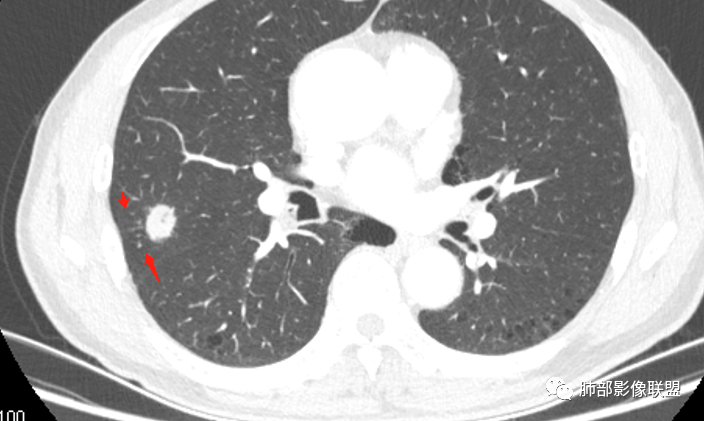

影像学改变:

1.右肺上叶后段类圆形结节影,密度不均,有坏死空洞,坏死比较彻底,内外壁都较清楚。

2.病灶有浅切迹,没有深分叶,毛刺大多细长且柔软。

3.可见棘状突起及胸膜牵拉,但未见胸膜凹陷。

什么意思?结节影有牵拉的动作,但似乎“出工不出力”,收缩力羸弱!

4.病灶轻到中度强化。病灶内血管走行较完好,病灶旁血管局部显示粗大。

5.支气管关系不确定。

6.灶周见小结节影(卫星灶),边界不甚清晰。